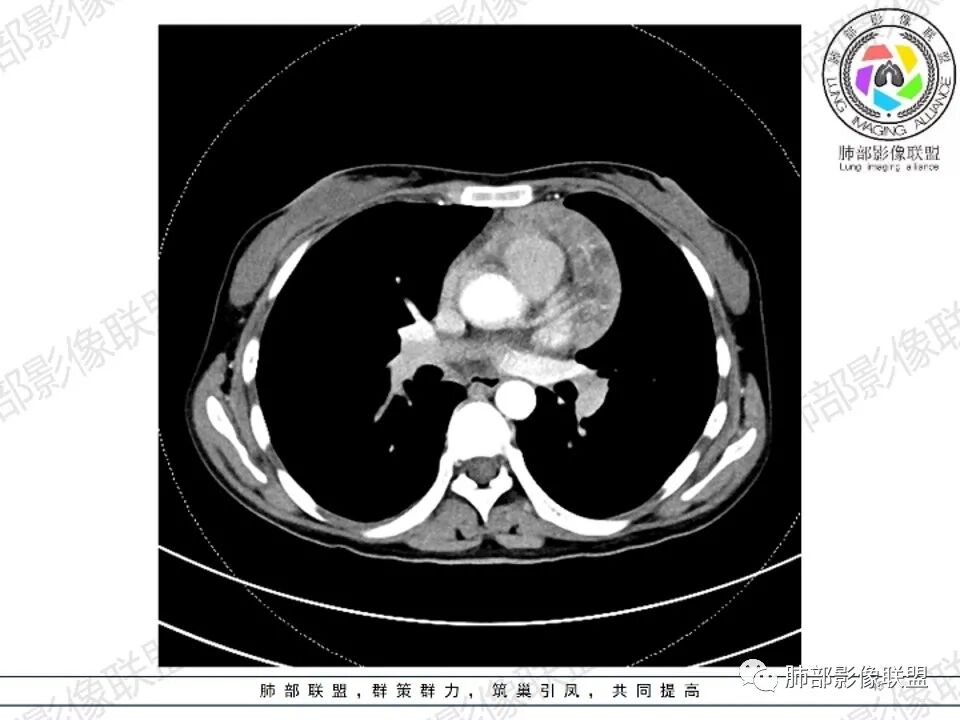

1、概述:又称巨淋巴结增生症,血管滤泡淋巴结增生,是少见的非典型淋巴增生疾病;病因不明,但有两种学说:第一种认为霍奇金病的变异型,有潜在的恶性;第二种认为是由炎症或某些未知抗原引起的淋巴反应性增生。局限型,常见于青少年;系统型,老年人,AIDS,导致全身症状如发热、贫血及淋巴瘤。

2、病理:①血管透明型,占80%~90%,滤泡内和滤泡间淋巴组织增生,滤泡中心含大量透明性的毛细血管;②浆细胞型,占10%~20%,以显著成片的浆细胞浸润为主,周围绕以免疫母细胞;③中间型,为上述两种类型的混合存在,可见于多中心型。

3、影像学表现:显著肿大强化的淋巴结,常局限性分布;当患者无或仅轻微症状,纵隔内和腹膜后出现单个慢性巨大肿块,CT平扫示肿块边缘清楚,实质密度均匀,尤其是肿块呈显著强化和邻近大血管一致时,提示本病的可能。即使实质密度不均匀,中心液化坏死,但实质部分呈显著强化,与邻近大血管相似时,在鉴别诊断中仍然要考虑到本病的可能。

4、显著强化的淋巴节可能:Castleman病;结节病;结核;转移淋巴结:肾细胞癌,甲状腺癌,肺癌,肉瘤,黑色素瘤